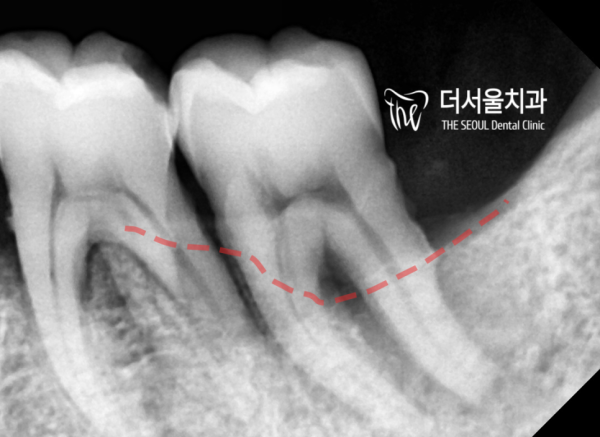

확대한 엑스레이 사진으로 확인해보겠습니다.

좌측은 사랑니 앞의 어금니 치관의 1/2가 썩어있고

우측 사진은 치조골 염증에 의해 치조골퇴축이 생겼습니다.

Let's check with the enlarged X-ray.

On the left, 1/2 of the molar crown in front of the wisdom tooth is rotten

In the right picture, alveolar bone degeneration is caused by alveolar bone inflammation.